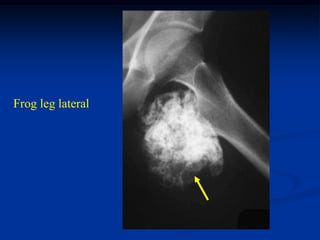

Case #590

12 year female

periosteal chondroma

proximal femur

Frog leg lateral